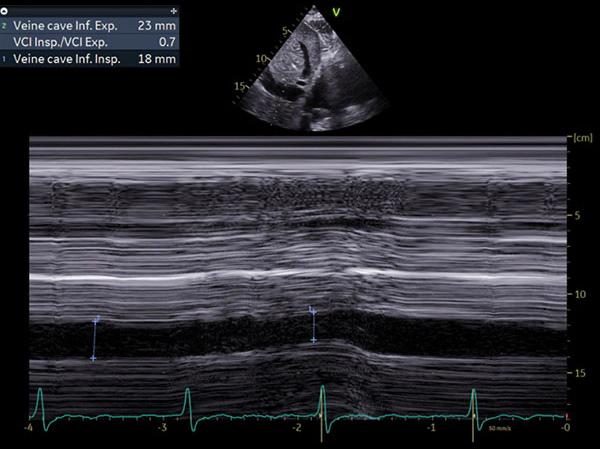

Figure 4 : VCI dilatée non compliante

- Phénotype typique : petite cavité VG, hypertrophie modérée, dilatation OG sévère, profil mitral, VCI dilatée